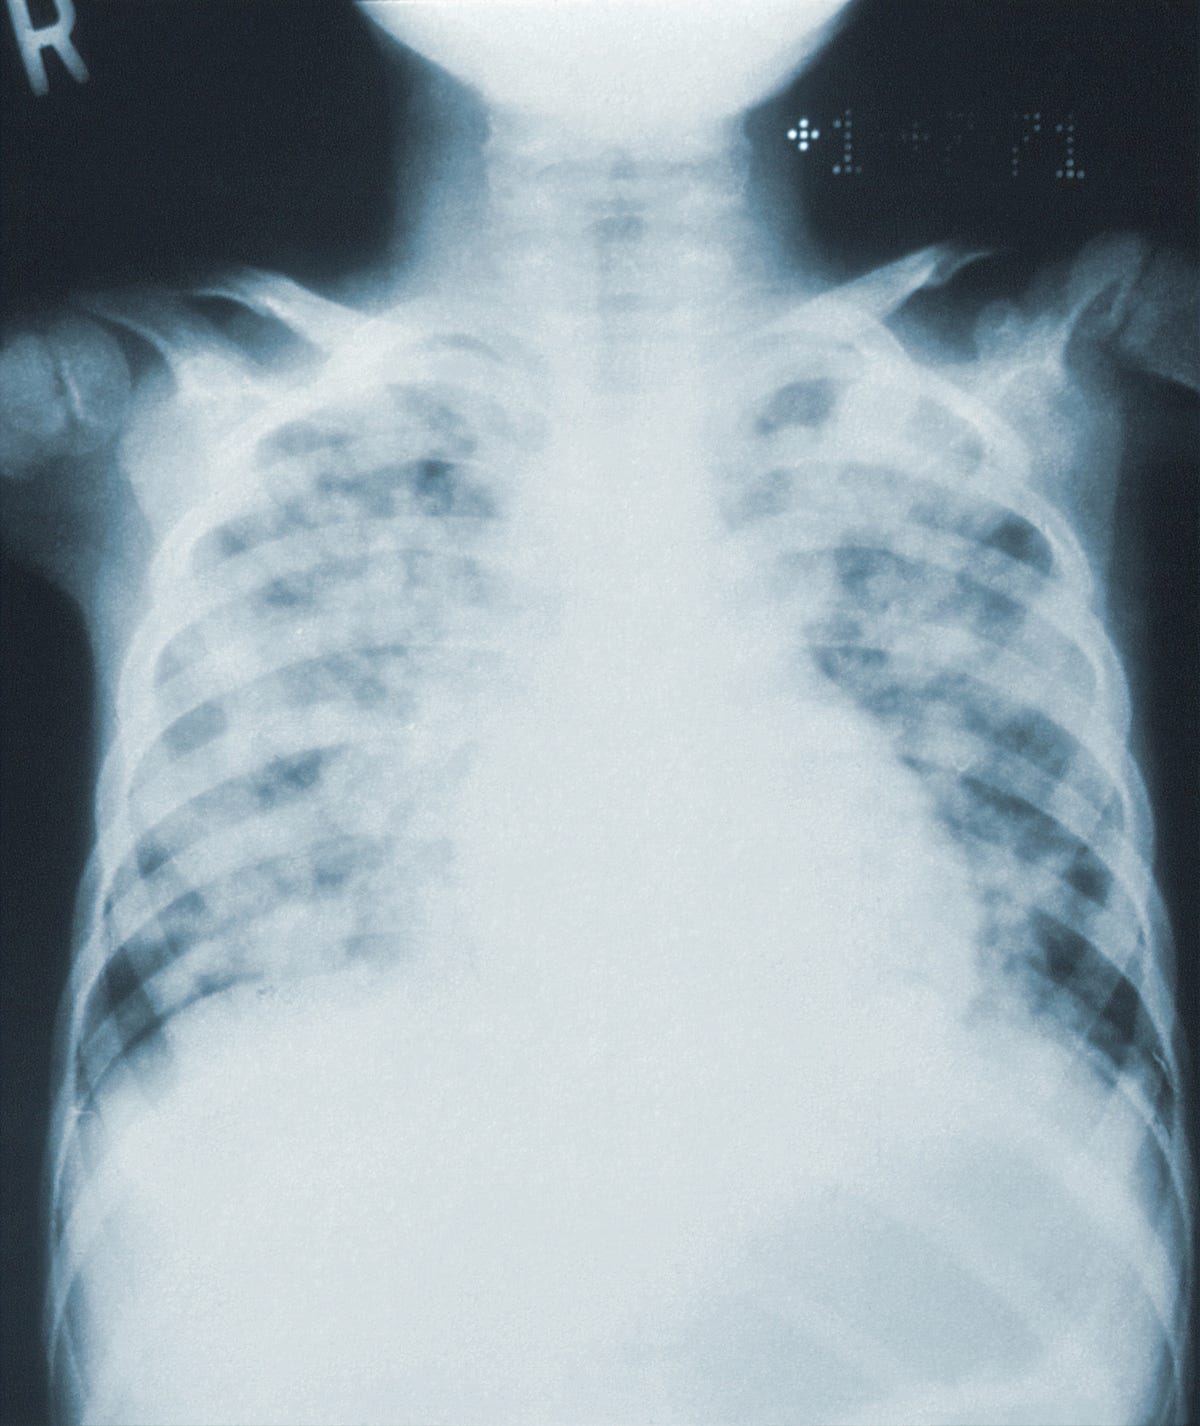

Lung Collapse Chest X Ray